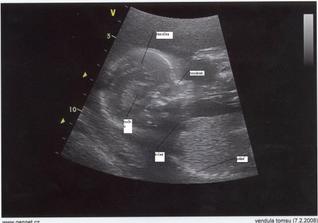

Ve 20tt jsme museli absolvovat odběr plodové vody - vše dopadlo v pořádku, mimi je zdravé a pohlaví - znát nechceme 🙂) Také jsme byli na velkém ultrazvuku - mimi měřilo 20cm a vážilo 400g.

31.4. - kontrola + UTZ ve 30tt, vše v pořádku, mimi už je hlavičkou dolů, takže čeká na start 🙂, váží přes 1.5kg. Pohlaví pořád vědět nechceme, ale tatínek tam prý viděl pinďu, tak to jsem teda zvědavá 🙂 K otokům nohou se ve vedru přidaly i otoky rukou, což je velmi nepříjemné, ale snad už to vydržím 🙂